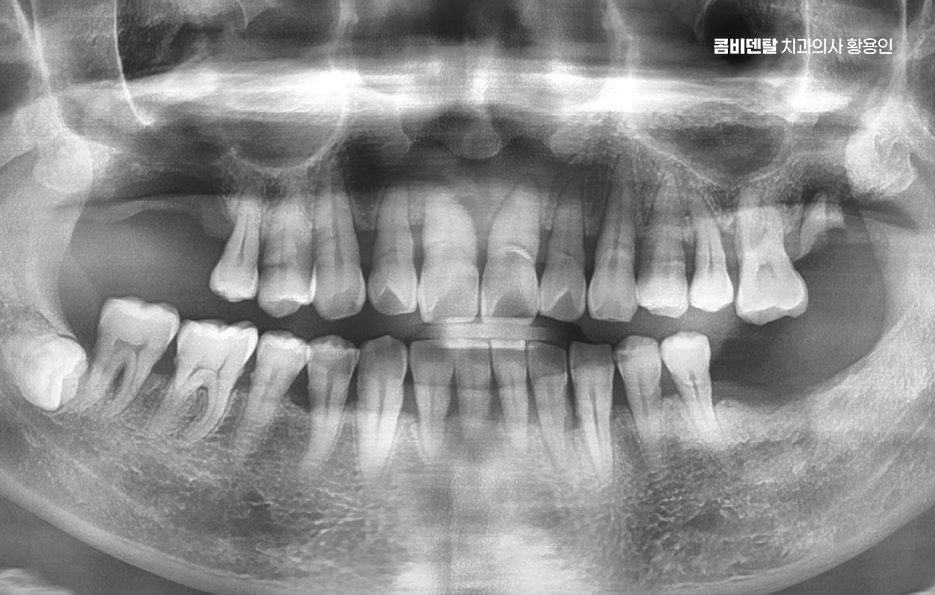

노년기에 자연치아를 잃게 되는 가장 흔한 원인은 치주질환으로 특히 60대 이후부터는 장기간 관리되지 않은 치주염이 진행돼서 결국 치아가 흔들리거나 빠지게 되는 경우가 많으며 일부는 오래된 보철물이나 충치가 원인이 되기도 하는데 자연치아가 하나 빠지면 단순히 그 부위만의 문제가 아니며 주변 치아들이 그 공간으로 쓰러지거나 이동하게 되고, 전체 치열이 무너지기 시작하는 거예요

그러면 한두 개의 상실이 전체 구강 구조를 무너지게 만들고, 결국은 씹는 힘도 약해지며 고령일수록 이런 변화가 더 빠르게 진행되기 때문에, 빠른 대응이 중요할 수 있었어요